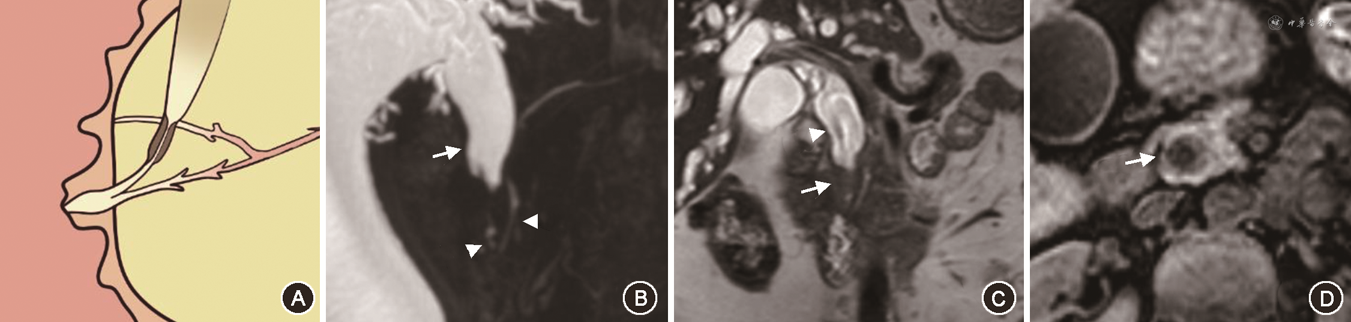

在对有意义单因素指标的分析中,笔者将PAC的MRI征象进行总结,最后归纳为十二指肠乳头结节型、胰腺肿块型、胆总管壁增厚型、壶腹部肿块型及胆总管腔内结节型5种表现类型。十二指肠乳头结节型MRI征象为位于十二指肠腔内的病灶,多为等信号,在十二指肠乳头形成突入腔内的结节,MRCP上胆总管及胰管扩张呈双管征,胰胆管角度较小,双管征走行呈平行或聚拢(图1)。胰腺肿块型MRI征象为胰腺内低信号肿块,MRCP上胆总管及胰管单独或同时狭窄截断可分别出现双管征、三管征、四管征,截断胰管周围可见扩张侧支,肿块引起胰胆管角度增大,管征呈分离走行(图2)。胆总管壁增厚型MRI征象为胆总管远段管壁增厚,近段胆管扩张,MRCP上胰管较少扩张,近段扩张胆管、梗阻下方远段胆总管与胰管呈三管征(图3)。壶腹部肿块型在MRI图像上表现为壶腹部跨壁生长的肿块,可与胰腺、十二指肠肠壁分界不清,但较少使十二指肠乳头表现为结节型,MRCP管征多为双管征(图4)。胆总管腔内结节型在MRCP图像上远端胆总管内见结节样充盈缺损伴胆道梗阻,远段胆总管、近段扩张胆总管及胰管呈三管征(图5)。

Fisher精确概率法结果显示,IPAC与PPAC在MRI影像5分型的差异具有统计学意义(P<0.001)(表4)。经调整检验水准后的 Bonferroni 法两两比较结果显示,十二指肠乳头结节型与胰腺肿块型、胆总管壁增厚型及壶腹部肿块型的差异均具有统计学意义(均P<0.005)。IPAC多表现为十二指肠乳头结节型(15/21,71.4%)(图1),PPAC更多表现为胰腺肿块型(18/38,47.4%)、胆总管壁增厚型(9/38,23.7%)或壶腹部肿块型(9/38,23.7%)(图2, 3, 4),IPAC(2/21,9.5%)与PPAC(0,0)均较少表现为胆总管腔内结节型(图5)。